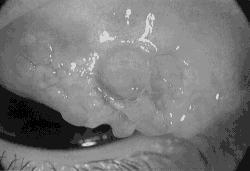

Zu den bekanntesten Formen allergischer Bindehautentzündung zählen Heuschnupfen-Konjunktivitis, Frühjahrs-Konjunktivitis und die Konjunktivitis bei endogenen Hautexzemen, also solchen, die nicht auf äußere Einflüsse zurückzuführen sind. In allen Fällen handelt es sich um langwierige Entzündungen, die aber mit modernen Behandlungsmethoden sowie mit Disziplin und Konsequenz seitens des Patienten durchweg befriedigendbeherrscht werden können. Während bei der Heuschnupfen-Konjunktivitis die Zusammenarbeit mit einem Allergologen zur evtl. Desensibilisierung sinnvoll ist, hat eine solche Maßnahme bei der Frühjahrs-Konjunktivitis und bei der Konjunktivitis der Ekzematiker erfahrungsgemäß keine Erfolgsaussicht. Die therapeutische Kunst des Augenarztes besteht bei diesen letztgenannten, eher chronischen Bindehautentzündungen darin, den Patienten mit einem Minimum an wirksamer Therapie beschwerdefrei zu halten, ohne unerwünschte Nebenwirkungen zu riskieren. Der Patient sollte verstehen, daß es sich bei dieser Erkrankungsgruppe um sogenannte konstitutionelle Leiden handelt, die theapeutisch wirksam gemildert, aber nicht vollständig ausgeheilt werden können, da die Veranlagerung ererbt und unveränderlich ist.

Frühjahrs-Konjunktivitis